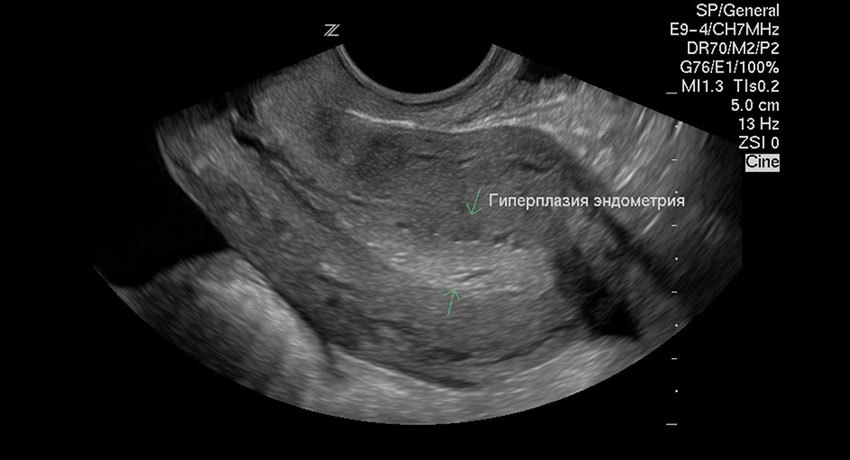

Скрининговый (общедоступный, безопасный) способ диагностики патологии эндометрия — ультразвуковое исследование. Кроме того, при подозрении на нее врач берет аспирационную эндометрия (тонким инструментом из полости матки берется фрагмент эндометрия и отправляется на гистологическое исследование. Процедура совершенно безболезненна).